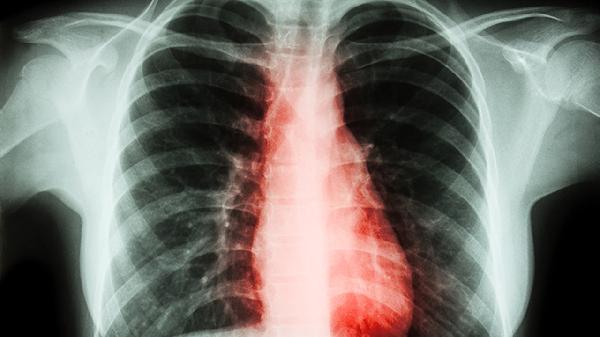

锻炼需在康复治疗师指导下进行,避免过度扭转或负重动作。建议结合定期影像学评估,侧弯角度超过20度需配合矫形支具。日常注意双肩背包交替背负,睡硬板床并采用仰卧位。青少年患者应保证每日1小时中高强度运动,补充维生素D和钙质促进骨骼发育。